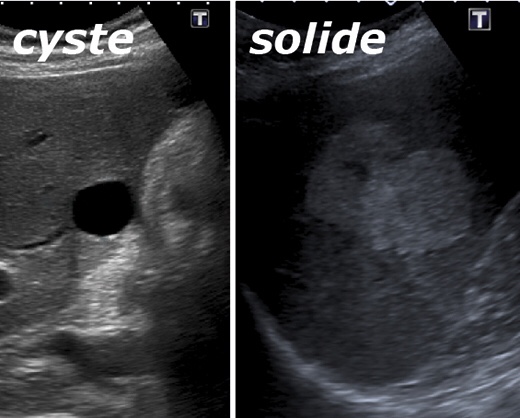

In totaal gebeurt dat 4x, elke borst in 2 standen. Daarna mag je door naar de volgende ronde voor de echo. De radiologe met koude vingers, smeert de op lichaamstemperatuur gebrachte gel op de borst want anders zou je er maar van schrikken (nee, die koude vingers waren prima😉). De ene na de andere zwarte plekje wordt zwijgend aangeklikt en opgemeten op het scherm…

Gelukkig kwam het verlossende antwoord direct van haar: het zijn cystes. Groot, dat zeker: 5,5 cm, maar gewoon gevuld met vocht. Of ik er last van had? Dan kon zij ze gelijk aanprikken en leeg laten lopen. Maar neuh… last heb ik er niet van dus laat maar ff zitten. Het is wel even genoeg kermis geweest dacht ik zo.